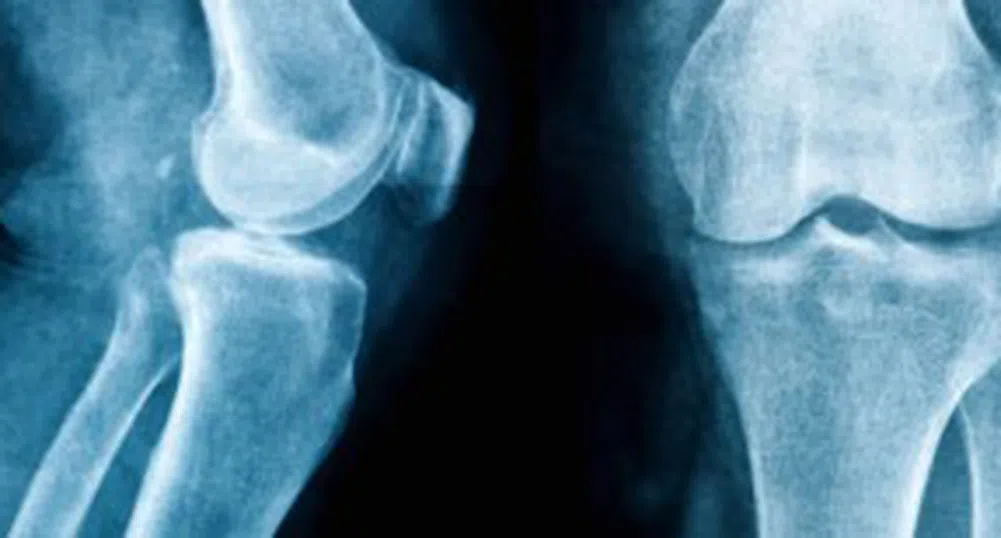

Хирурзи от Медицински университет в Льовен в Белгия доказаха съществуването на още едно сухожилие в колянната става.

В коляното има четири основни връзки, които помагат за стабилизирането му: две странични връзки и две централни сухожилия, наречени кръстни връзки. Но понякога тези връзки са ранени, особено честосрещано нараняване при спортистите. В много случаи, този вид увреждане се нуждае от операция. Въпреки това, много пациенти се оплакват дори и след операция, от болки и нестабилност на коляното.

За да разберат защо е така хирурзите ортопеди Стефан Клаас и Джоан Белман провеждат четиригодишни задълбочени изследвания. Те успяха да докажат съществуването на още едно сухожилие, което досега не фигурираше в анатомичните атласи.

Според тях, в 97% от човешките колене има такова сухожилие, което може да обясни защо лечението на разкъсана предна кръстна връзка никога не води до пълно възстановяване.

Тази констатация може да доведе до по-добро лечение на наранявания на коленните сухожилия. Освен това, двамата хирурзи вече работят по техника, с коят смятат, че ще постигнат пълно възстановяване на коленните стави при този тип травми.